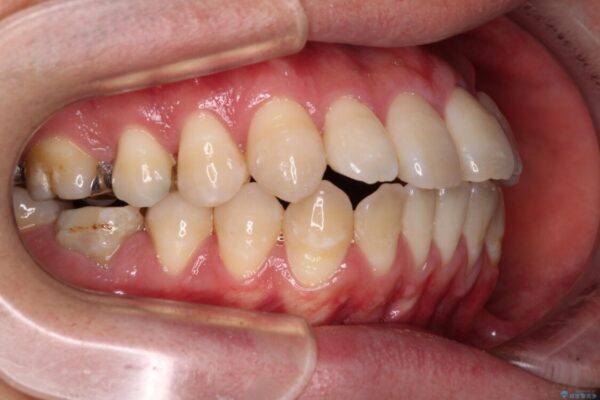

「横から見ると唇が前に出て見えるのが気になる…」 「マスクを外すのが恥ずかしい…」 そんな口元の突出感に悩まれてご来院された患者様。

精密検査の結果、上下左右の小臼歯4本を抜歯し、そのスペースに前歯を後方へ移動させる矯正治療をご提案しました。

治療前

• 口元の突出感を改善!目立ちにくいワイヤー矯正で自信を持てる自然な横顔に 治療前画像